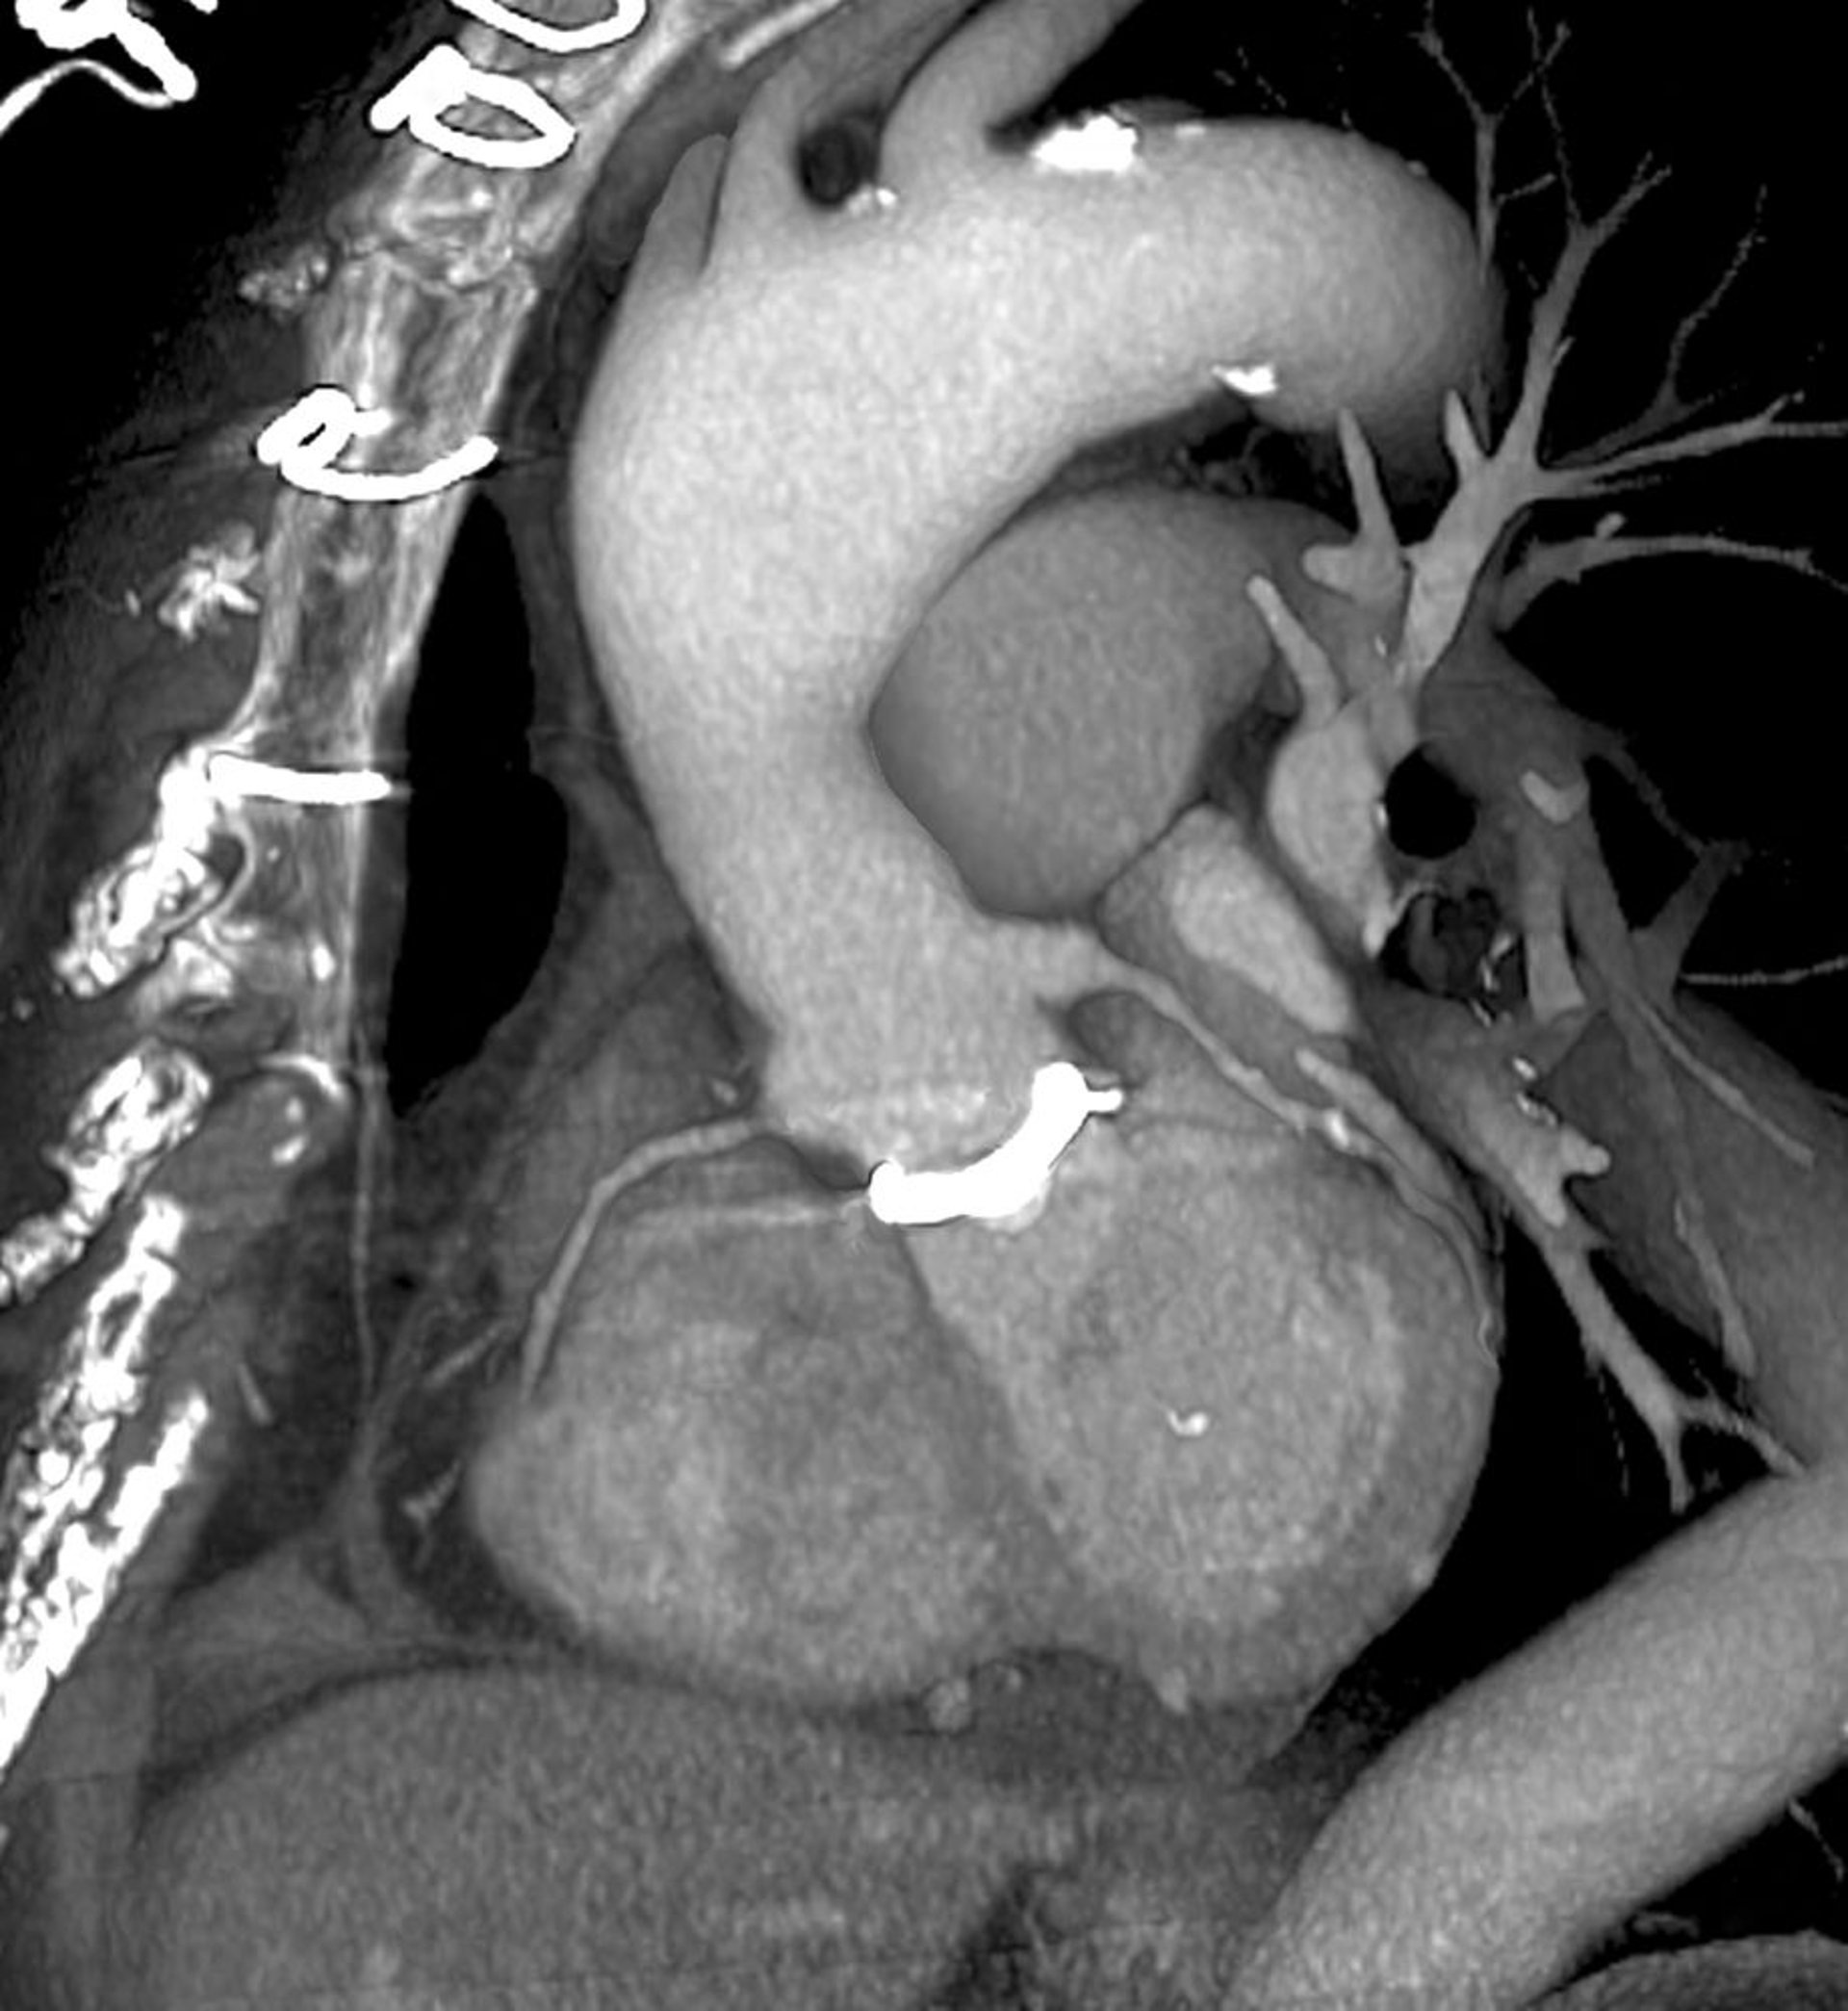

Сердечная КТ (трехмерное сканирование искусственного клапана сердца)

Данное изображение ─ это косая проекция левой стороны, если смотреть с фронтальной стороны грудной клетки (слева). Искусственный клапан сердца (белый) виден в центральной части снимка, где аорта (в центре вверху)соединяется с сердцем (в центре внизу). Швы, используемые для закрытия грудной клетки, видны в левом верхнем углу.